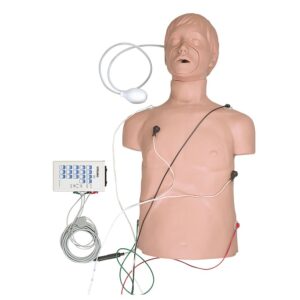

Simulaids Ausculation Trainer

Ausculation Trainer, Practice Board and Smartscope™

Ausculation Trainer, Practice Board and Smartscope™